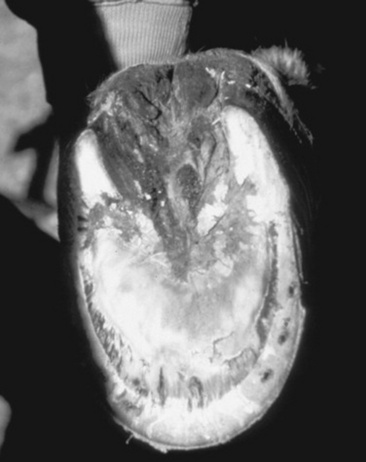

Peracute cases may have total degeneration of the secondary epidermal laminae, which causes a separation between the primary epidermal laminae of the hoof wall and the collagen fibers of the corium. Abscessation may occur in the necrotic laminae or subsolar tissues. The distal phalanx may sink or may be rotated ventrally with respect to the hoof capsule, and the tip may penetrate the sole (Fig. 38-31). Severe cases are accompanied by fractures of the solar margin, osteomyelitis, or severe resorption of the distal phalanx. The necropsy findings generally demonstrate a variable degree of elongation of the epidermal laminae, which depends on the severity and duration of the problem (Fig. 38-32).

image image

Fig. 38-31 A, Midsagittal section from the foot of a horse with a normal digit. Note the distance between the dorsal surface of the dorsal cortex of the distal phalanx (open arrows) and the inner surface of the hoof wall (arrows). The dorsal surface of the hoof wall and dorsal cortex of the distal phalanx are parallel. Compare with Figure 38-30, A. B, Midsagittal section from the foot of a horse with severe laminitis, a “sinker.” Note the increased distance between the dorsal surface of the dorsal cortex of the distal phalanx (open arrows) and the inner surface of the hoof wall (arrows). Also note that the distal phalanx has not rotated with respect to the hoof wall. Compare with Figure 38-30, B. C, Midsagittal section from the foot of a horse with severe laminitis. There is approximately an 18-degree rotation of the distal phalanx, and its tip has penetrated the sole (curved arrow). Note the increased distance between the dorsal surface of the dorsal cortex of the distal phalanx (open arrows) and the inner surface of the hoof wall (arrows). Compare with Figure 38–30, C.